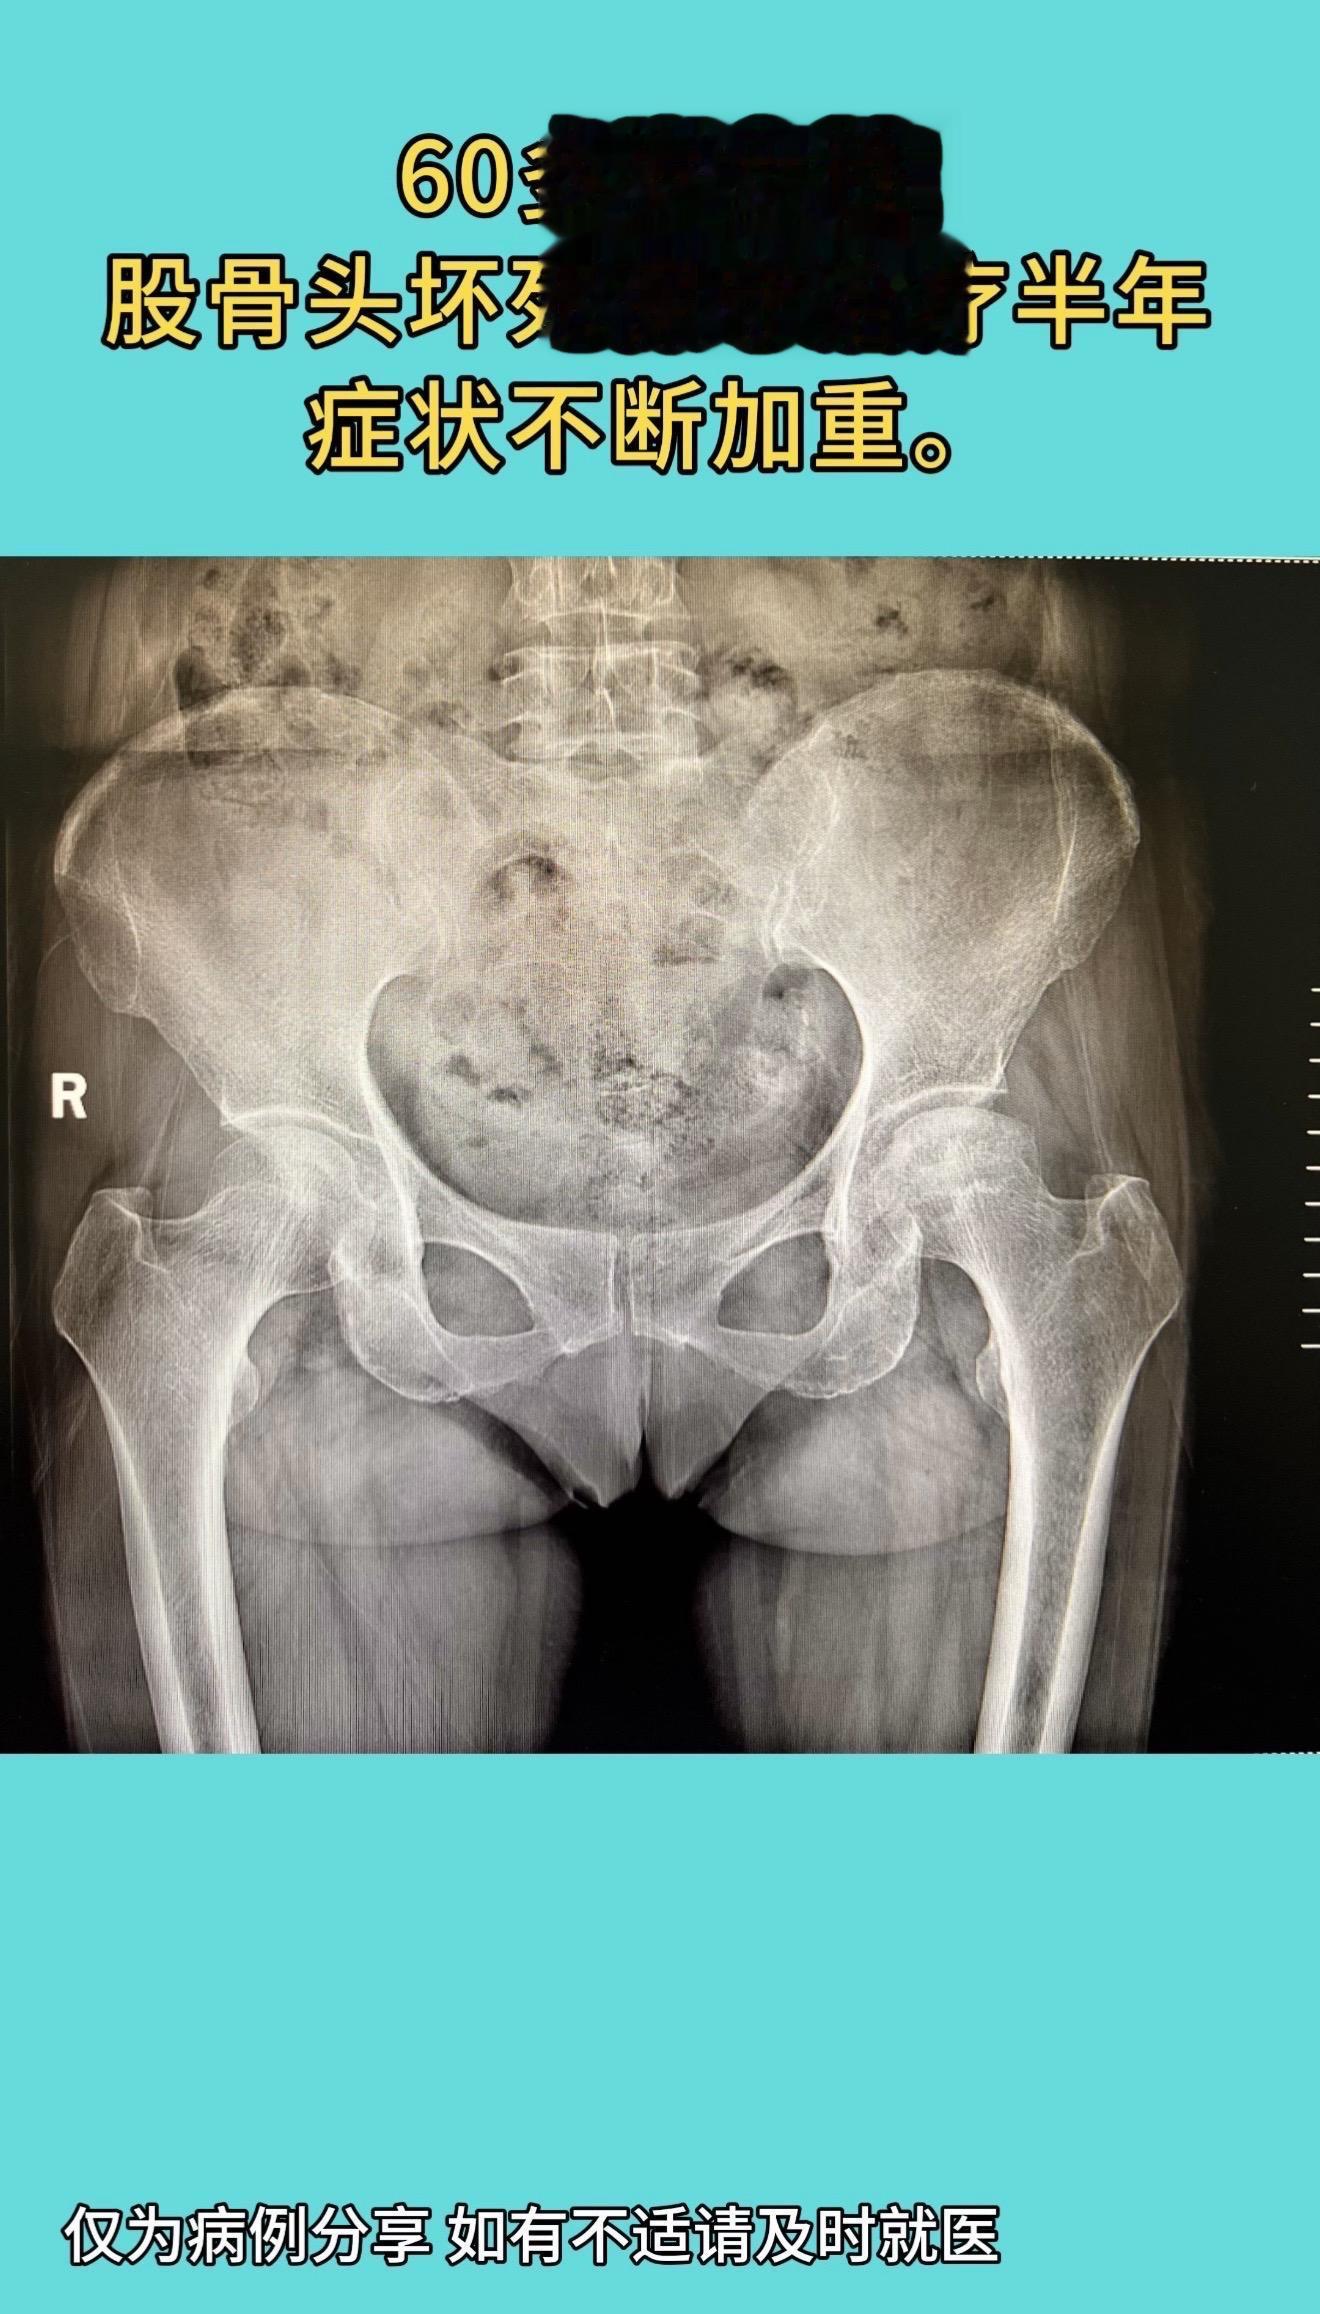

国内顶尖专家做的一例全髋置换手术:片子漂亮的像一件艺术品,术后症状缓解,双下肢等长,活动度佳。60多岁女性,股骨头坏死保守治疗半年,症状不断加重。